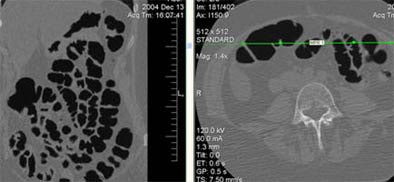

![]() |

| A 44-year-old woman (first-degree relative of a colorectal cancer patient) underwent screening VC. Conventional colonoscopy two years earlier was incomplete due to dolichocolon. Immediately after prone decubitus positioning at the end of the exam, the patient reported abdominal pain, nausea, and stimulus to vomiting; a cold sweat was also observed. ECG did not show alterations of the cardiac cycle, blood pressure was normal, and a sustained bradycardia (50 bpm) was observed. VC data analysis confirmed the presence of dolichocolon and revealed overdistension of the small bowel in the supine (above) and in the prone decubitus positions (below). All symptoms resolved in 30 minutes. All images courtesy of Dr. Emanuele Neri. |